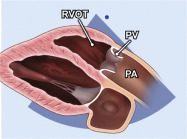

| 2.4. Mặt cắt trục dài cạnh ức phóng đại van hai lá |

||||||||

Cửa sổ siêu âm cạnh ức

Mặt cắt trục dài cạnh ức Đặt hộp phóng đại vào vị trí van hai lá Ghi được toàn bộ chuyển động của hai lá van, đoạn gần của dây chằng và vòng van. |

Van hai lá (MV)

Nhĩ trái (LA) |

|||||